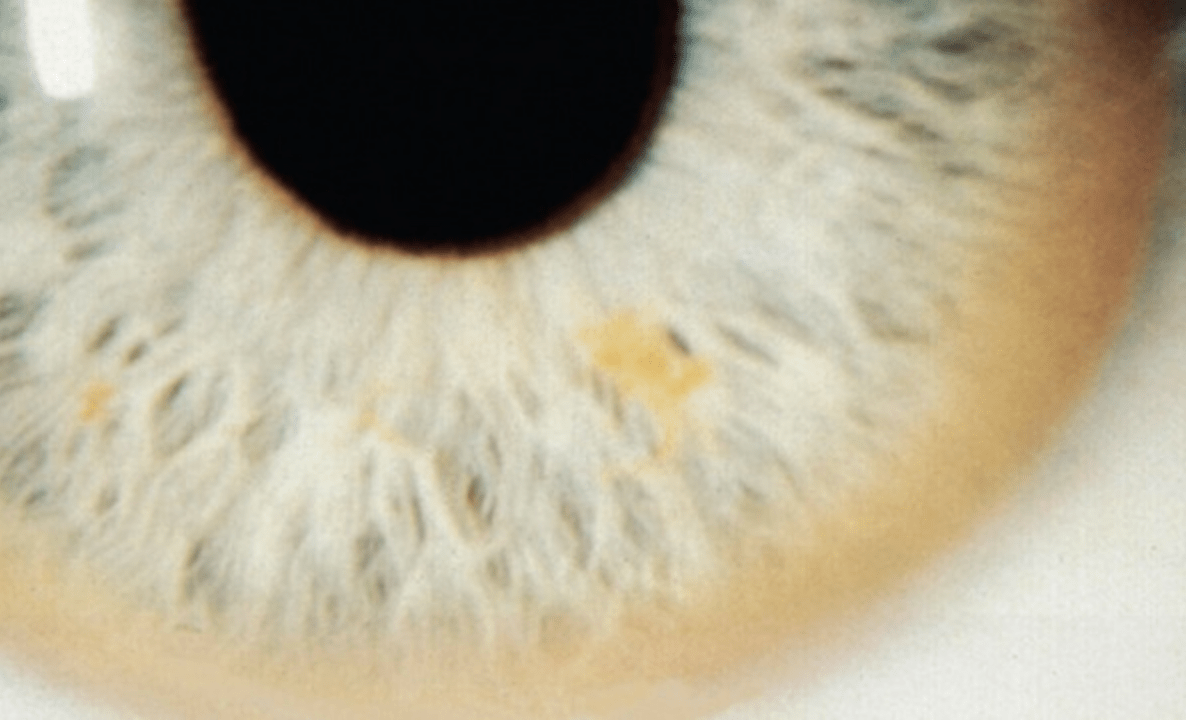

Diagnosis on a test?

Wilson disease - Sunflower cataract

BONUS:

- Autosomal recessive

- Kayser Fleischer ring